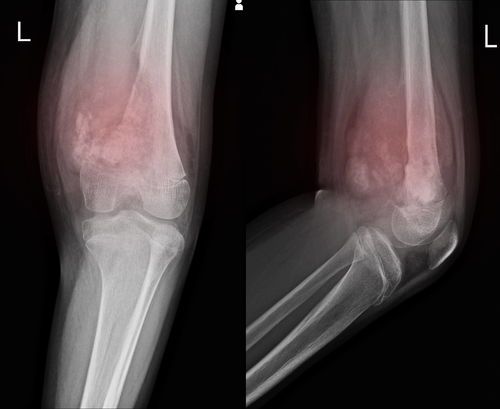

骨肉瘤-打篮球扭伤膝盖,肿了一个月不消,骨科医生让拍片发现了

在篮球场上挥洒汗水的青少年,膝盖扭伤肿胀似乎是成长的“标配”印记。多数情况下,这确是韧带或软组织的问题,休息几周便能恢复。当肿胀持续一月不退,普通的冰敷与休息失效时,一个更危险的信号可能正在被忽略——它可能不再是简单的运动损伤,而是被称为“沉默骨骼杀手”的恶性骨肿瘤,如骨肉瘤,发出的早期警报。本文将通过一个整合临床案例的叙事,深入剖析骨肉瘤如何伪装成常见损伤...